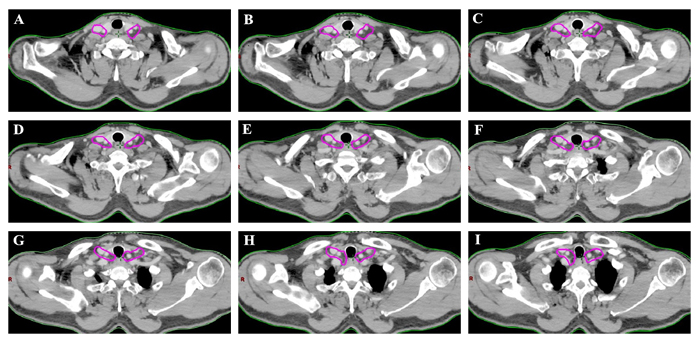

In our study, the lymph node group with a probability of 10% or more (an empirical cutoff value) of being involved was recommended containing in the CTVn. [12, 14] On the basis of on our findings, 94.4 % (84 of 89 patients) occured the LNM in subgroup II and/or subgroup III region . The anatomic distribution of the 151 LNs indicated that more than 95% of the metastatic LNs was located in the group II and III region. Therefore, the lower cervical group II and III regions had higher rate of LNM, and those subgroup region should receive prophylactic radiation therapy.

This atlas serves as an available template for target delineation of lower cervical region in the elective treatment of lower cervical nodes in definitive RT/CRT. The suggested CTVn of lower cervical target volumes according to the results are showed in Figure 3.

Figure 3: The suggested CTVn for the lower cervical region according to the results. The targets should include lower cervical group II and III.

It was reported that lymph nodes usually locate in the vascular spaces. [19-21] Definition the radiation target volume of lymph node based on vascular rather than bone anatomy could decrease the normal tissue irradiation and minimize treatment related toxicity. In the present research, we gave accurate information for the anatomical spatial distributions and clinical probabilistic incidence of metastatic lymph nodes onto a template CT image according to diagnostic image in EC patients. Based on our analysis, 94.4 % (84 of 89 patients) patients had subgroup II and/or subgroup III region lymph node metastasis, in which 75.3% patients had subgroup III region lymph node metastasis, followed by the subgroup II lymph nodes 69.7% (62 of 89 patients). In contrast, only 5 of 89 patients (5.6 %) with subgroup I and subgroup IV region lymph node metastasis, which suggests that these two subgroups may be spared for irradiation. Besides, total 151 nodes were considered to be clinical metastatic in the lower cervical region in those patients and the atlas showed that the most involved sites of lower cervical LN recurrence were the subgroup II (68 of 151 nodes) and subgroup III (77 of 151 nodes) region, which should be precisely included in the prophylactic volume.

In conclusion, our findings proposes helpful information for radiation oncologist about the delineation of lower cervical region clinical target volume. Based on the present study, prophylactic irradiating to lower cervical areas is recommended for patients with deeper tumor invasion, the mediastinal level 1, 2, and 4 station LNM and the more number of LNM. The atlas showed that, for the lower cervical area, the subgroup II and III region should be precisely covered in the target volume and the subgroup I and IV may be spared for minimizing the toxicity.